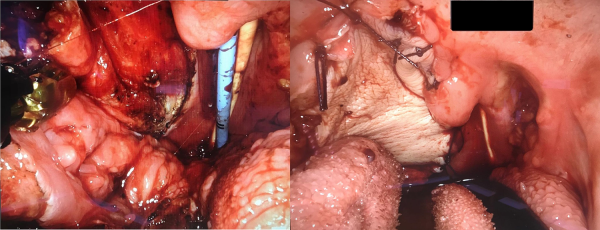

Results

Mean postoperative stay was 14 (range 6-27 days) days with 2 patients discharged within 10 days of surgery. Two patients experienced postoperative complications. Patient 1 required a prolonged inpatient stay due to a persistent tracheocutaneous fistula following tracheostomy decannulation with a resultant hospital acquired pneumonia which was managed with first-line antibiotics. Patient 2 had a minor episode of hemorrhage from his lingual frenulum which was managed nonsurgically. Mean duration of enteral feeding was 11 days (4-23 days) with nasogastric tube removal and resumption oral diet occurring in all patients prior to discharge. All patients underwent early tracheostomy decannulation (mean postoperative interval 3 days, range 3-8) with no episodes of acute airway distress.

Histopathological examination demonstrated complete R0 clearance of the primary lesion in all cases with no margin involvement. All specimens demonstrated p16 positive SCC which was metastatic to 4/8 lymph nodes in one patient without extracapsular spread.

The mean duration of follow-up is 12 months with the first and second patients showing no signs of recurrence on clinical examination or cross-sectional imaging. A posttreatment CT in the third patient revealed likely new lymph node involvement in the right neck and mediastinum, and as a result, they have been commenced on Nivolumab immunotherapy as a third line treatment. Postoperative outcomes are summarized in Table 2.